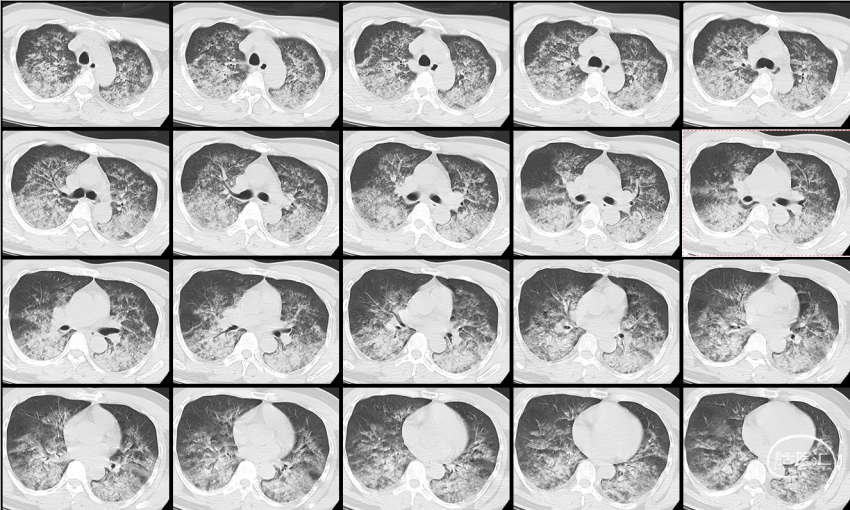

肺CT:

双肺多发炎性改变,符合吸入性肺炎表现。

术后4天,肺部CT显示吸入性肺炎明显好转